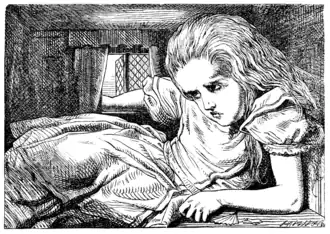

| The perception a person can have due to symptoms of pronounced micropsia. See § Comparison with Alice's Adventures in Wonderland, below. Image from that same novel. | |

Alice in Wonderland Syndrome, a neurological condition associated with both micropsia and macropsia, is named after Lewis Carroll's famous 19th century novel Alice's Adventures in Wonderland. In the story, the title character, Alice, experiences numerous situations similar to those of micropsia and macropsia. Speculation has arisen that Carroll may have written the story using his own direct experience with episodes of micropsia resulting from the numerous migraines he was known to have. It has also been suggested that Carroll may have had temporal lobe epilepsy.